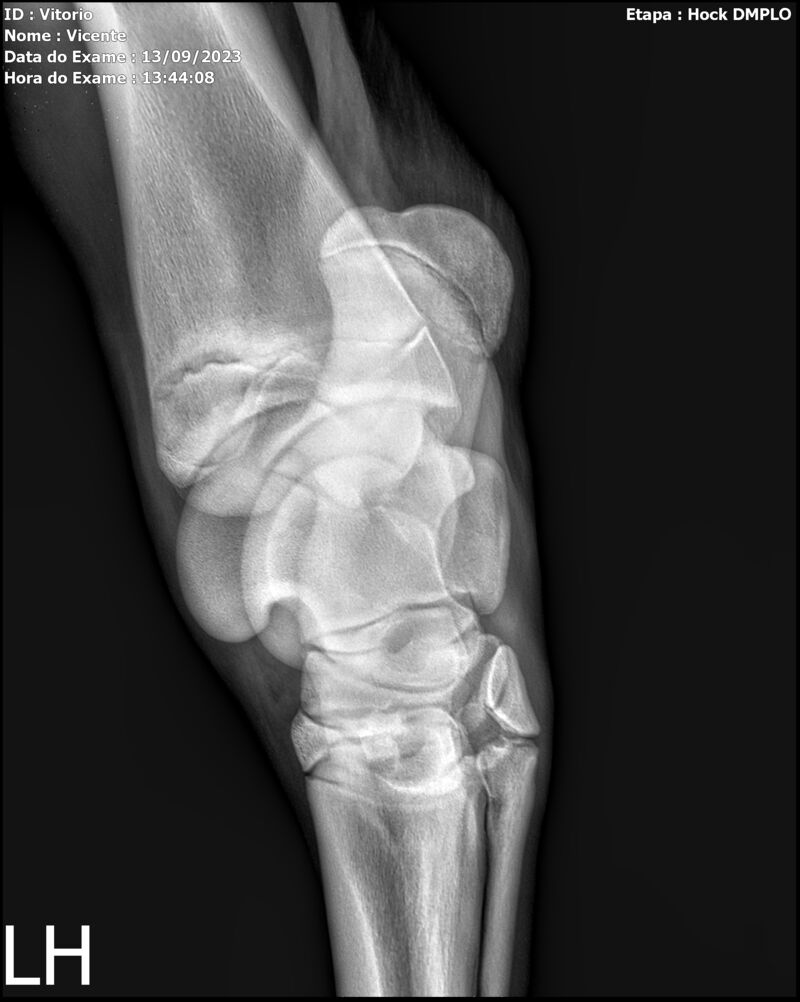

LOTE 13

THUNDER ZC

Raça: BRASILEIRO DE HIPISMO

Sexo: MACHO - POTRO

Nascimento: 17/09/2022

Altura Aproximada: 1,54

Pel.: CASTANHO

Registro: EM AND

Vend.: VICENTE CONTE

Local : PORTO FELIZ/SP